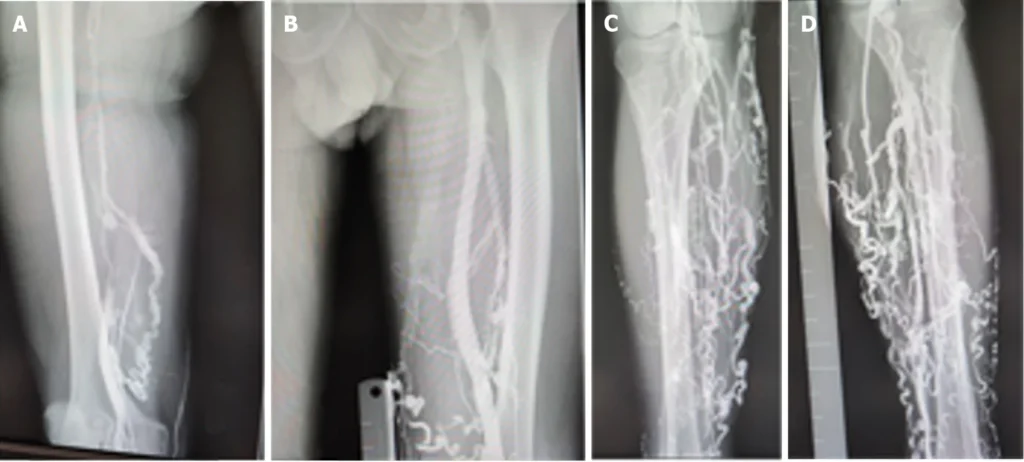

How varicose veins are diagnosed properly

The most important test is Venous Doppler (Duplex Ultrasound). It is not a formality—it’s the backbone of correct treatment planning. Doppler helps identify which vein is leaking, how severe the reflux is, and whether the great saphenous vein (GSV), small saphenous vein (SSV), or other segments are involved. It also helps rule out clot-related concerns and guides the choice between laser, RFA, glue therapy, or sclerotherapy.

If you are looking for a varicose vein clinic in Jaipur you want a place that takes care of everything. They should check what is wrong, with you treat you and then check on you again. At VascuCare Diagnostics & Interventions they usually start by asking you about the problems you have every day and what you do at work like if you stand all day travel a lot or sit for hours. Then they use a machine called Venous Doppler or Duplex ultrasound to look at the varicose veins and find out where the problem is.

Based on Doppler findings, Dr. Rakesh Kumar Kumawat recommends the most suitable non-surgical approach—such as Laser (EVLT), RFA, glue therapy, or sclerotherapy—depending on your vein anatomy and stage. The idea is to treat the root cause and reduce the chance of recurrence.